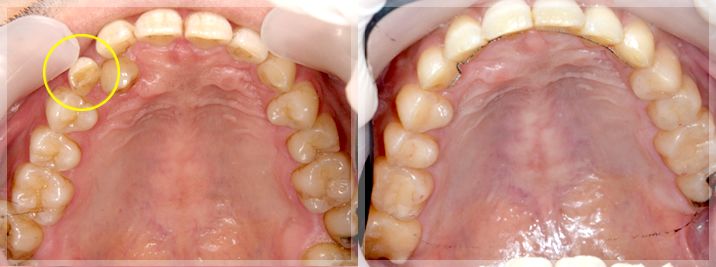

晩期残存乳歯の改善

| 術前 | 術後 |